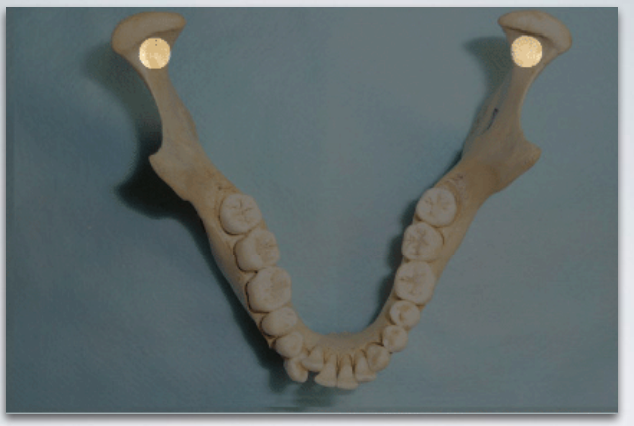

target site for which injection?

standard inferior alveolar nerve block AND lingual nerve block (can anesthetize both nerves using single injection at this site)